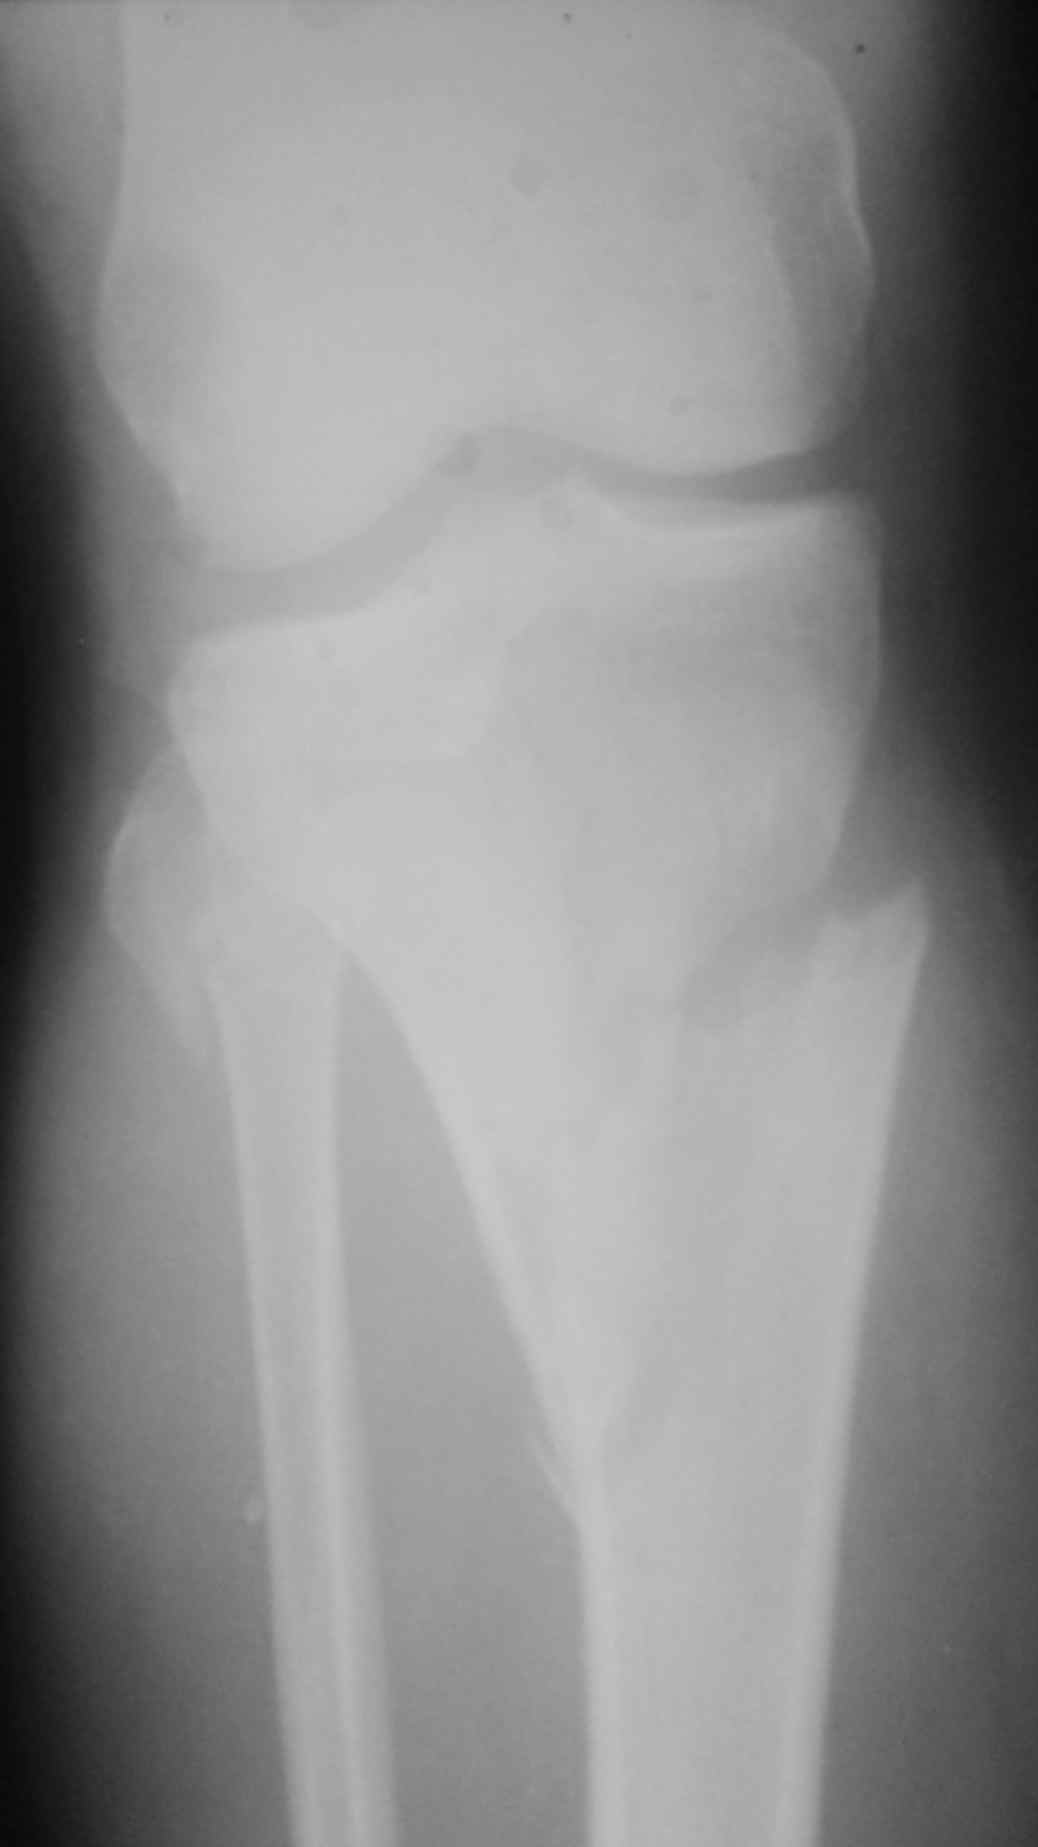

Похожий случай, вчера прооперировали. Непрямая репозиция, малоинвазивный остеосинтез без обнажения зоны перелома.